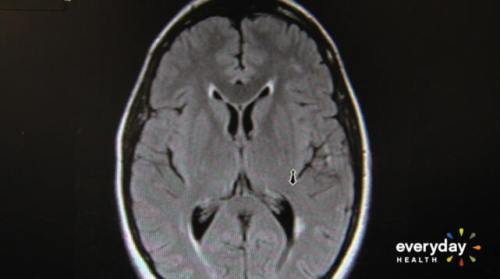

Deep brain stimulation offers hope for patients with essential tremors, but the surgeons must be guided by the patient himself. For Roger Frisch, that meant playing the violin while having brain surgery.